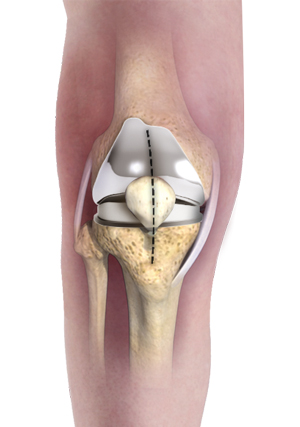

Total Knee Replacement

What is Total Knee Replacement? Total knee replacement, also called total knee arthroplasty, is a surgical procedure in which the worn out …